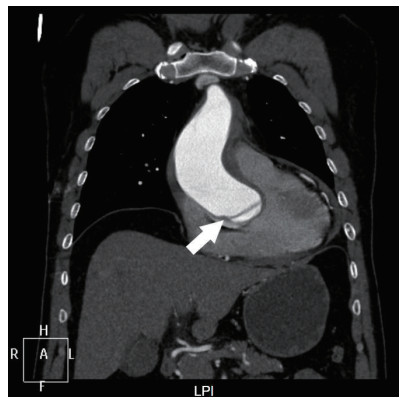

| 图 3 主动脉CTA冠状面上撕裂瓣膜表现(箭头所示) |

本案例中首诊医院仅通过心电图异常结果便给予抗血小板、抗凝治疗并非合理甚至可能加速患者死亡,尤其在既往无冠心病高危因素、冠心病史且年龄较轻的患者中及时完善超声检查可以减少误诊机率。而本例患者主动脉CTA影像中未清晰显示出主动脉瓣结构导致放射科医师误将撕裂内膜判读为瓣膜影,且瓣膜撕裂范围局限于右冠窦内,D-二聚体无升高表现。以上多重因素导致患者病情延误诊治。